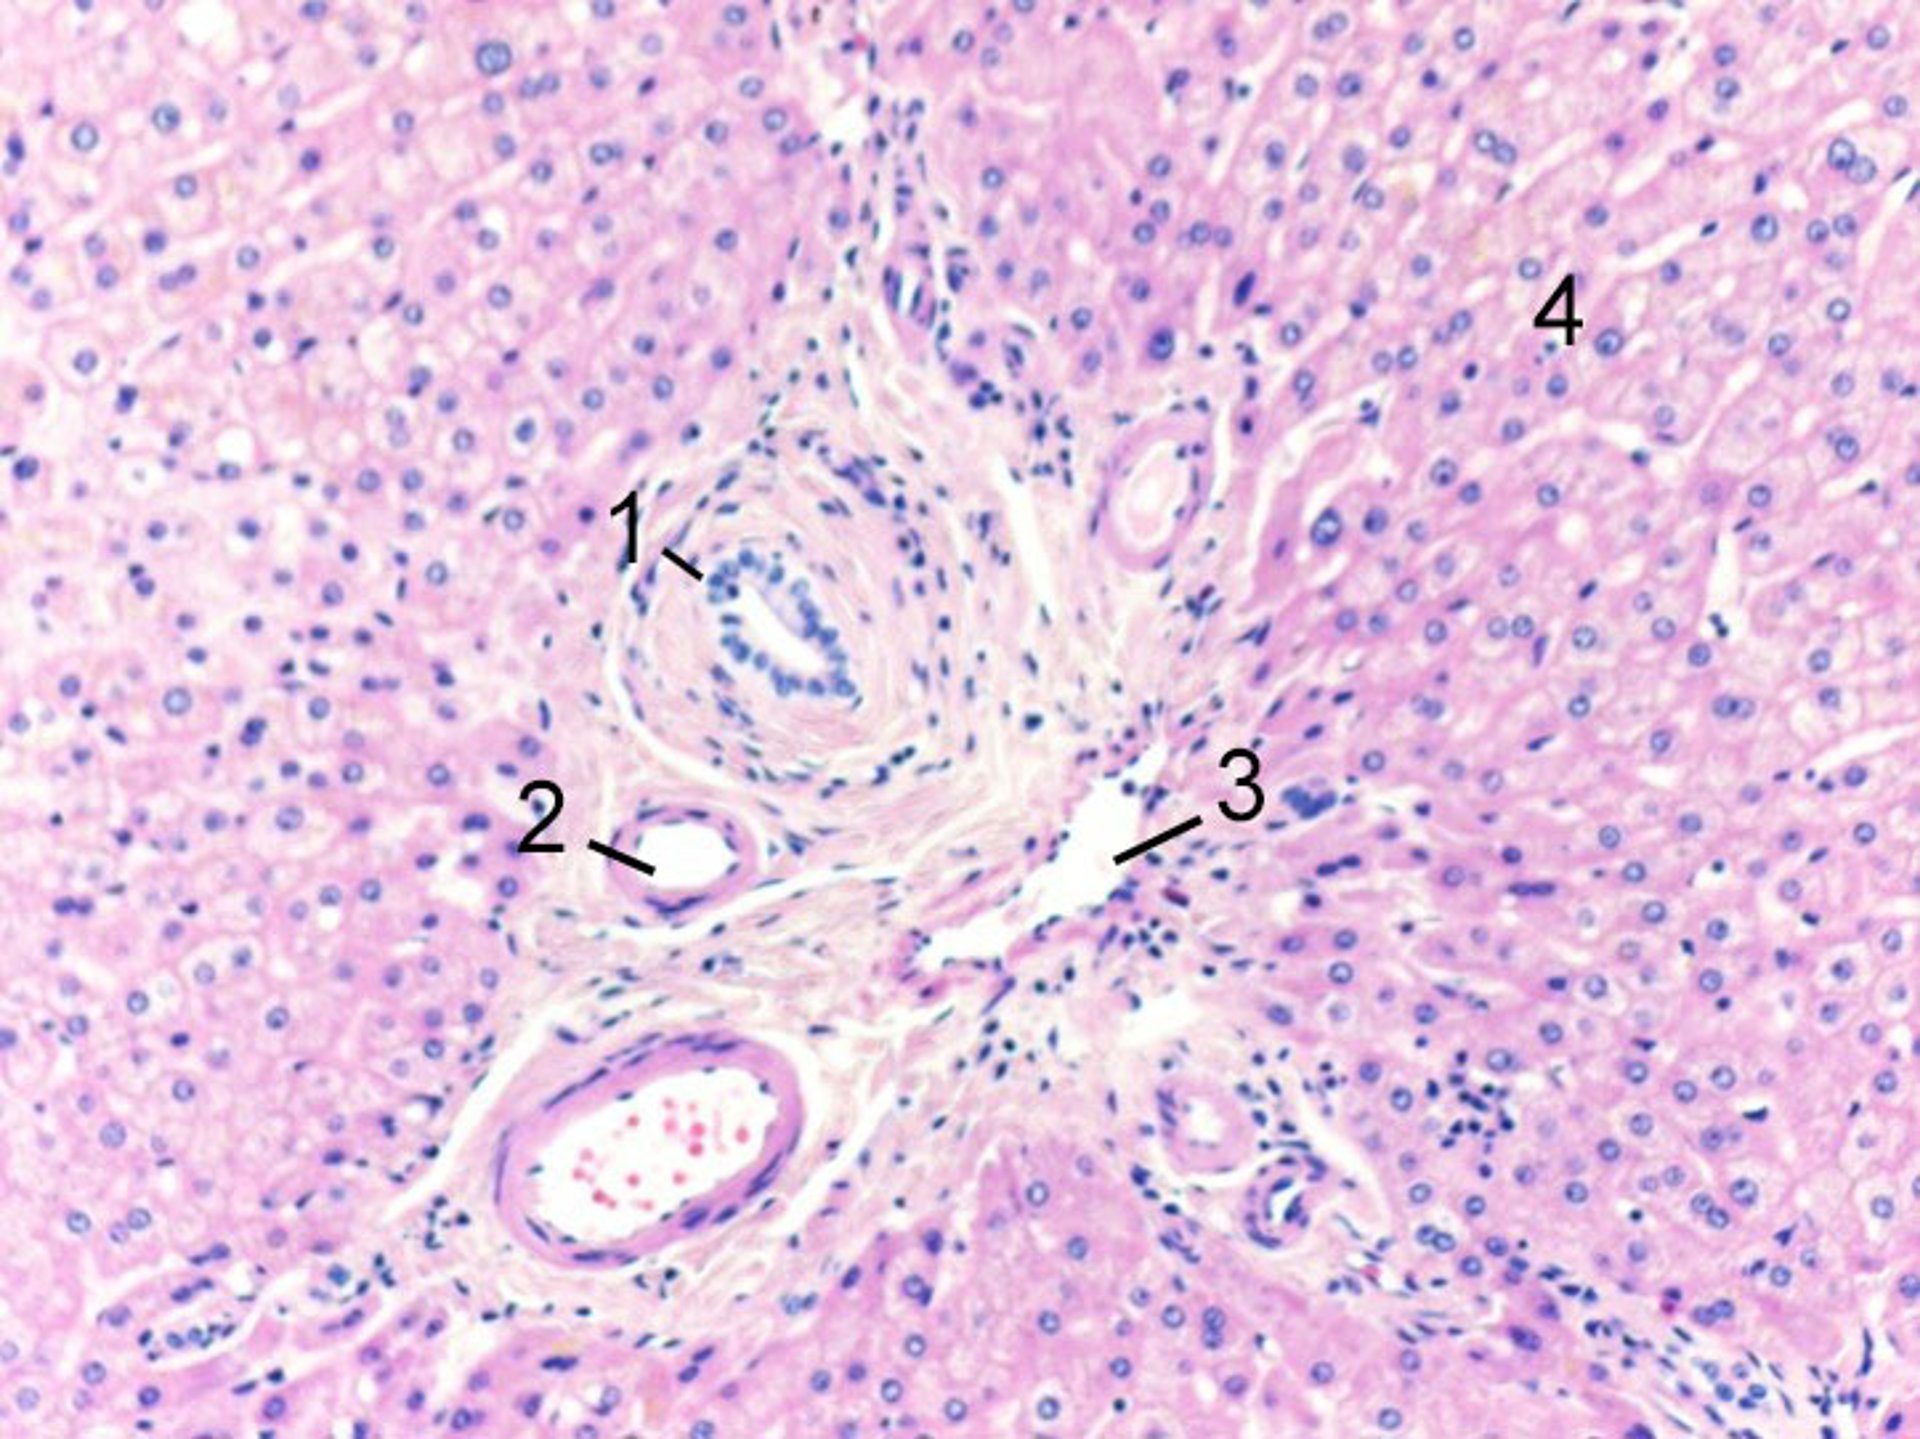

At the cellular level, hepatocytes are organized within a lobule, which is a hexagonally shaped groups of cells with a hepatic vein at the center, and portal triads around the periphery. The portal triads consist of adjacent and parallel terminal branches of bile ducts, portal veins, and hepatic arteries. Blood flows from the hepatic artery and portal vein (in the portal triads) in the periphery, through the sinusoids between the hepatocytes, toward the central vein. Consequently, hepatocytes at the center of the lobule are most susceptible to ischemia because oxygen and nutrients have been extracted by hepatocytes as blood flows through the sinusoids from the periphery. Smaller channels, called bile canaliculi, drain bile secreted by the hepatocytes into the intrahepatic bile ducts at the periphery.

Image courtesy of Danielle Tholey, MD, and M. Isabel Fiel, MD, MS, FAASLD.